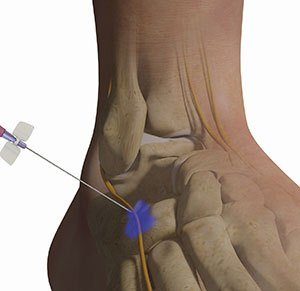

Nerve Entrapment Release

Frees compressed nerves to relieve pain, numbness, or weakness.